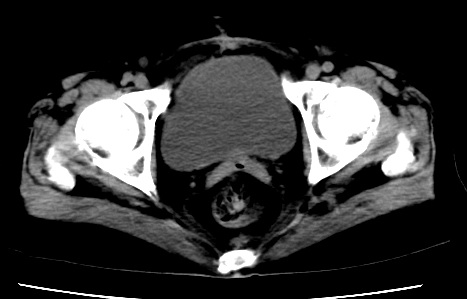

既往5年前卵巢癌行子宫及附件切除,右乳癌术后一年,考虑腹膜转移?

大量腹水,考虑腹膜转移。肝脏低密度灶。1囊肿,2转移。

1)结合病史,考虑腹膜及网膜转移瘤。2)肝脏多发性低密度灶,不排除转移瘤。3)大量腹水。

考虑卵巢癌行子宫术后复发,并肝、腹腔 、大网膜转移可能性大。

大量腹水。